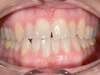

Cas 4 : Description

Chevauchement sévère. Traitement multibague sans extraction.

Avant

Après